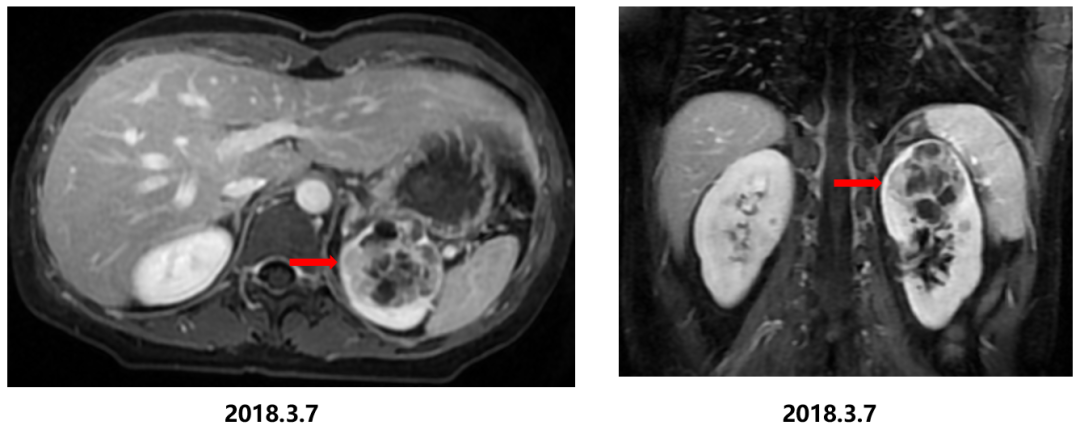

影像学检查:我院腹部增强MRI显示左肾上极占位病变,大小约为45x45x48 mm,考虑囊性肾癌可能性大。病灶未侵犯肾盂,未侵犯邻近血管,腹膜后未见肿大淋巴结。

△腹部增强MRI显示左肾上极占位病变